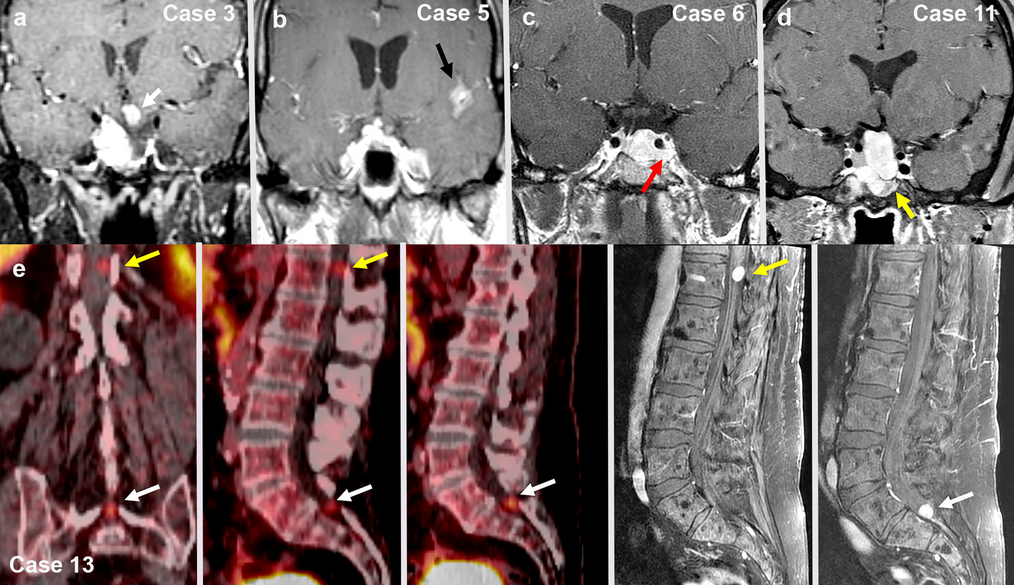

Cauda Equina Neuroendocrine Tumors with Ganglioneuromatous Elements are Best Classified as Composite Gangliocytoma/Neuroma and Neuroendocrine Tumor (COGNET)

Rapid Evolution of Metastases in Patients with Treated G3 Neuroendocrine Tumors Associated with NEC-Like Transformation and TP53 Mutation

Little is known about the morphomolecular features of G3 neuroendocrine tumors (G3NETs) under prolonged systemic treatment...

High-Grade Progression, Sarcomatous Transformation, and/or Metastasis of Pituitary Neuroendocrine Neoplasms (PitNENs): The UCSF Experience

Pituitary neuroendocrine tumors (PitNET) that metastasize comprise ~ 0.2% of adenohypophyseal tumors are aggre...